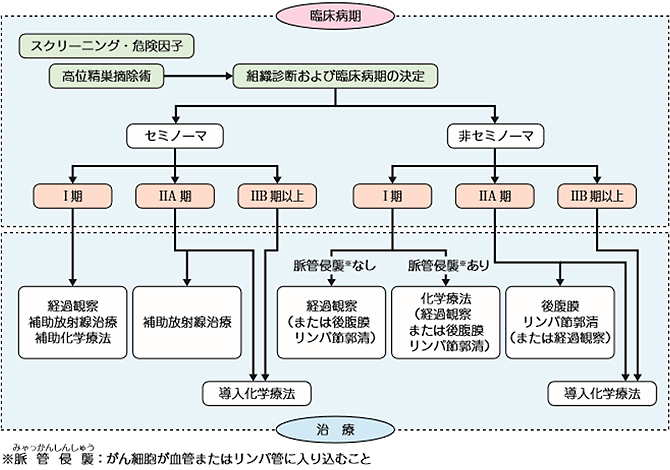

精巣腫瘍の治療方針

精巣腫瘍が強く疑われる場合、基本的には患側の精巣を摘出する手術を行います。手術で取り出した組織を顕微鏡で調べる(病理診断)と同時にCTなどの画像診断によって、腫瘍の種類と病期を確定します。それらの情報をもとに治療選択を行っていきます。